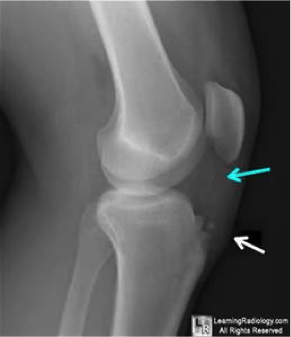

Is your child complaining of knee pain? If so, there is a chance it may be Osgood-Schlatter disease. According to the Mayo Clinic, a common cause of knee pain in youth is Osgood-Schlatter disease. Although the word "disease" is in the name, it is not really a disease, but rather an overuse injury. Osgood-Schlatter disease is an inflammation of the bone, cartilage, and/or tendon at the top of the shinbone where the tendon from the kneecap attaches. This inflammation can cause a painful lump below the kneecap in children and adolescents experiencing growth spurts during puberty.

Who is most susceptible to the condition? Osgood-Schlatter disease occurs most often in children who participate in sports that involve running, jumping and swift changes of direction such as soccer, basketball, figure skating and ballet. Since girls experience puberty earlier than boys, the age range of affliction varies by gender. Osgood-Schlatter disease typically occurs in boys ages 13 to 14 and girls ages 11 to 12. The condition usually resolves on its own, once the child's bones stop growing.